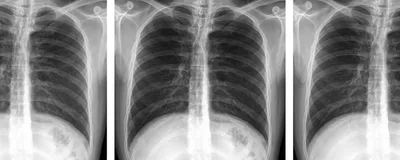

On August 15, we wrote about a “rare case report” published in Medicine in which authors claimed they had encountered a case of “ectopia cordis interna” and described an asymptomatic man with his heart located in his abdomen. Sleuths believed the case report plagiarized images from a 2015 satirical paper describing a condition of the same name.